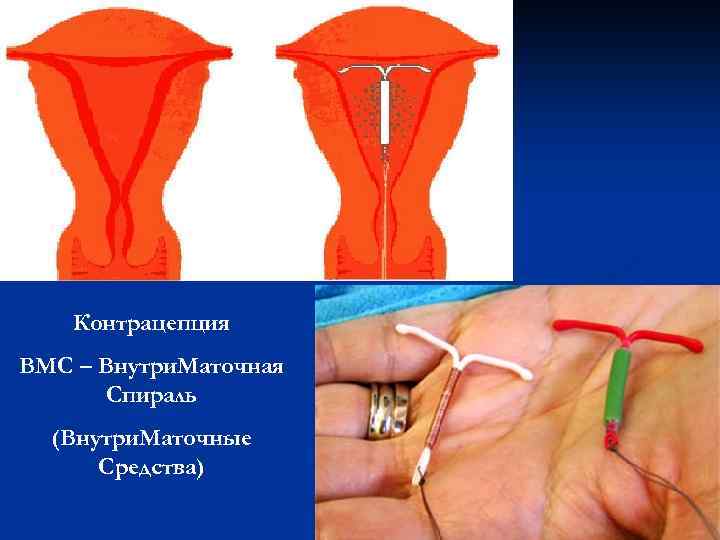

Контрацепция ВМС – Внутри. Маточная Спираль (Внутри. Маточные Средства)

Контрацепция ВМС – Внутри. Маточная Спираль (Внутри. Маточные Средства)